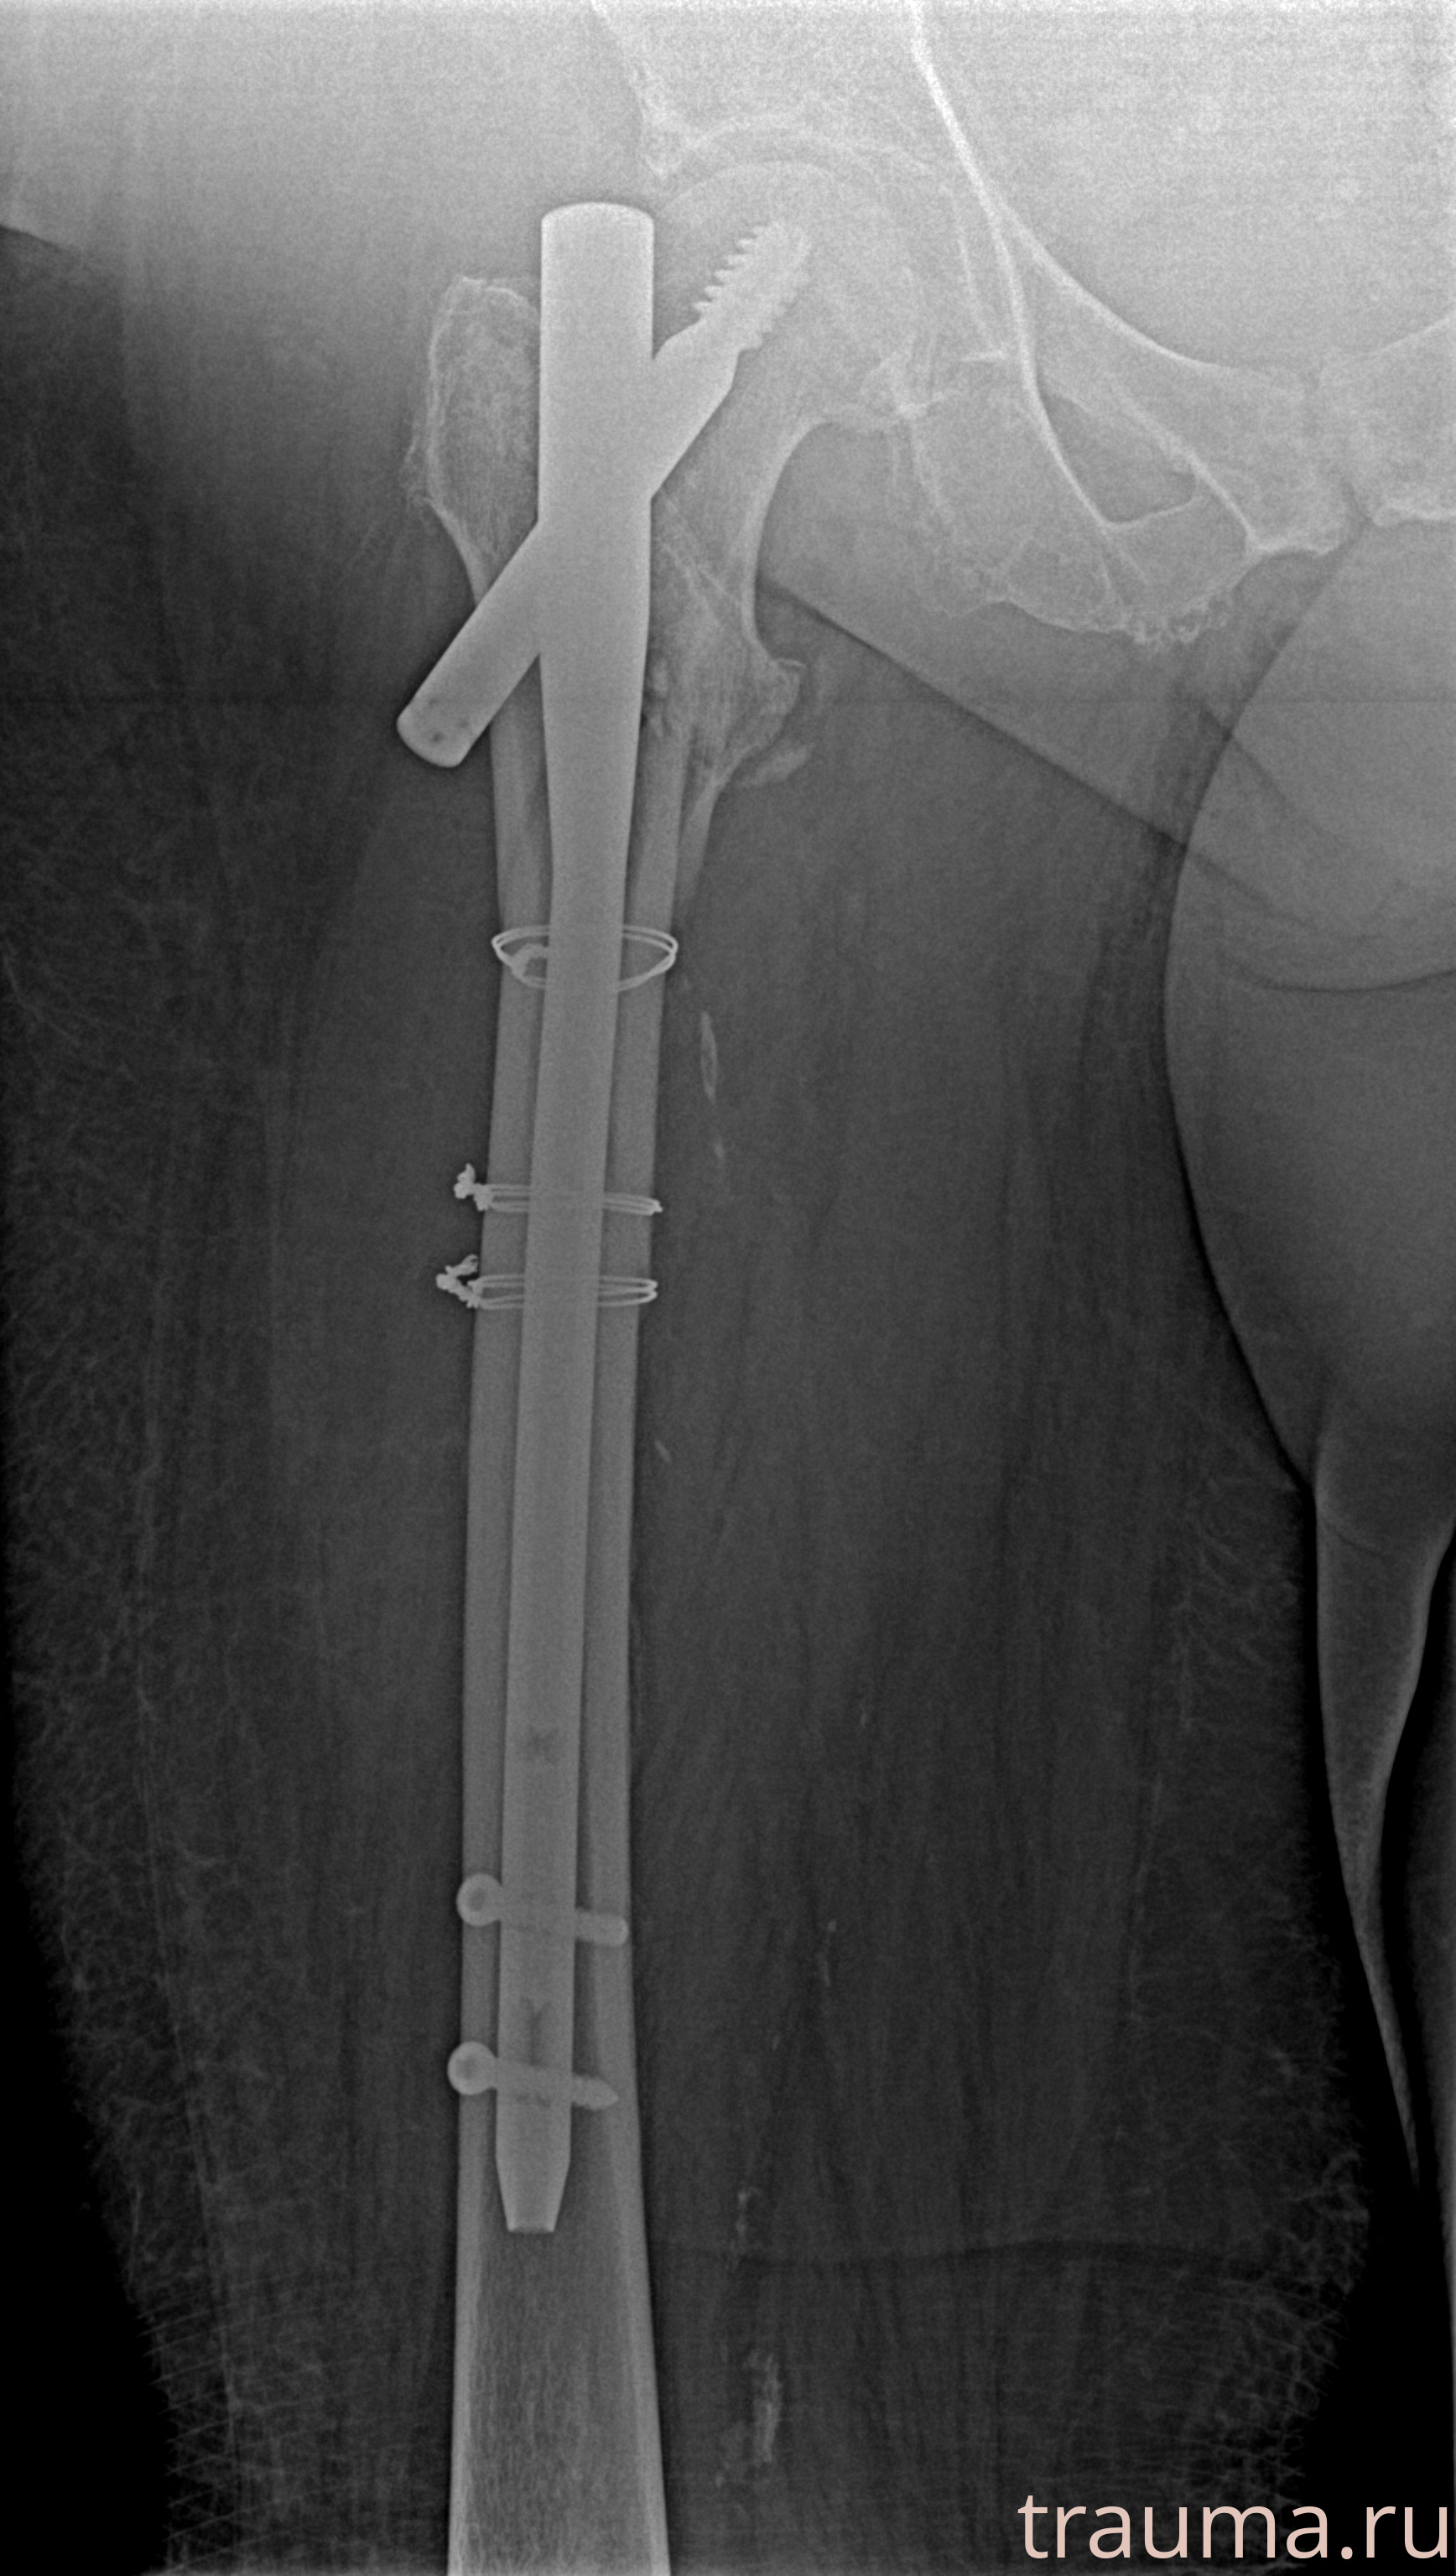

Рентгенограммы

Рентген на дому: по вашему адресу приезжает врач-рентгенолог, травматолог-ортопед с мобильным рентгеновским аппаратом, проводит диагностику травмы или заболевания, делает необходимые рентгенограммы, дает рекомендации по дальнейшему лечению. Получить качественные снимки в домашних условиях возможно благодаря уникальной методике, разработанной МосРентген Центром для института  Склифосовского